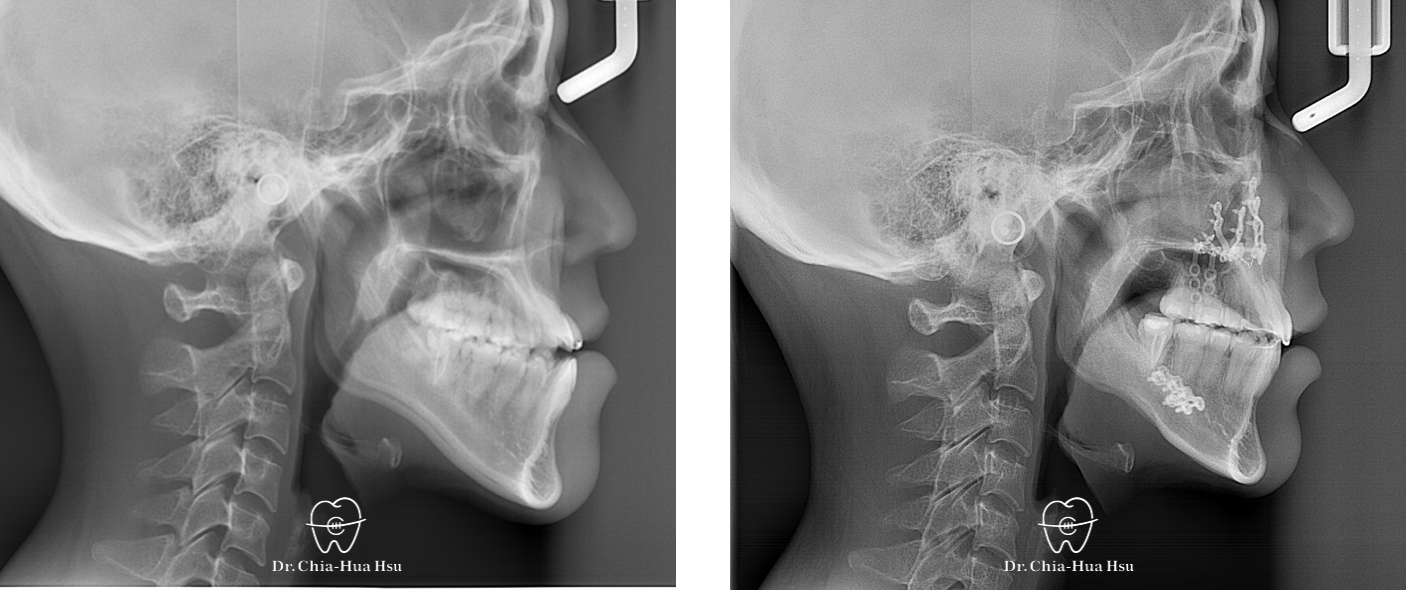

戽斗、前牙錯咬、開咬

成⼈矯正 | ⾦屬矯正 | 正顎⼿術

治療前

治療後